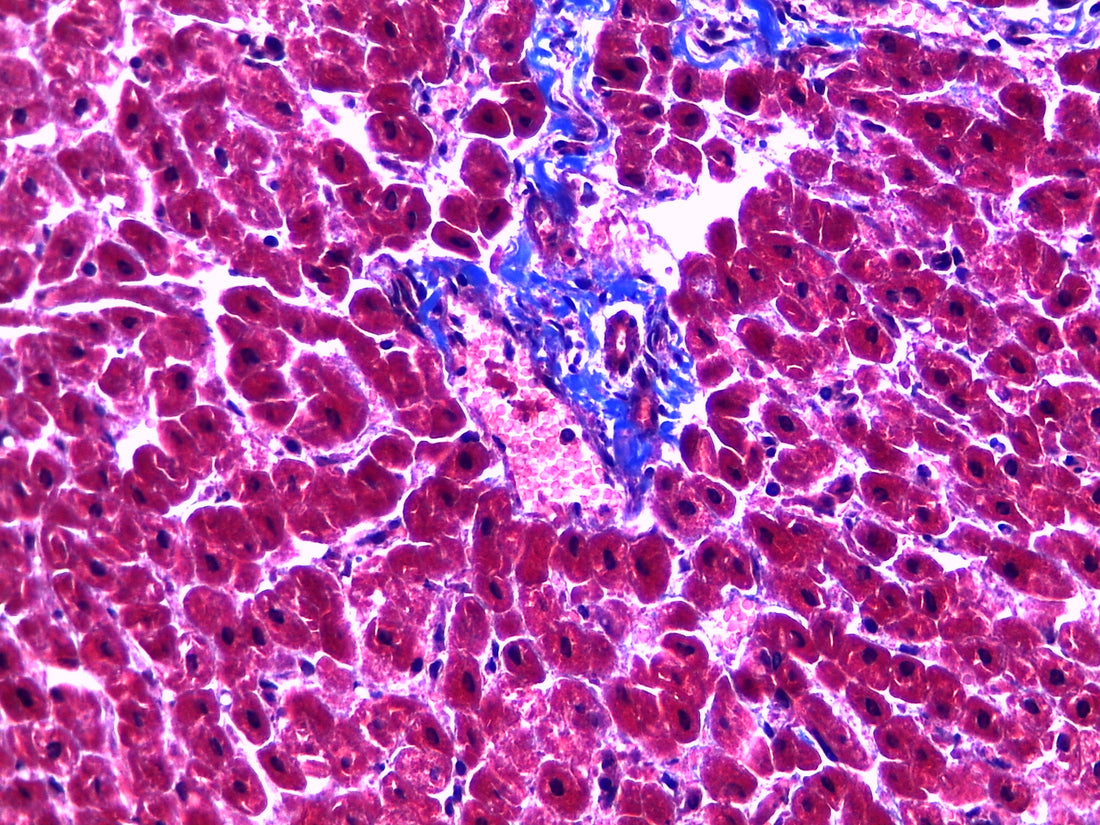

Under the microscope, nuclei appear dark blue, cytoplasmic structures such as muscle fibers and erythrocytes appear red, and collagen fibers appear blue-green. This allows for the visualization and differentiation of different tissue components.

Masson's trichrome stain is commonly used in the diagnosis of various diseases such as myocardial infarction, liver cirrhosis, and fibrosis. It is also used in research to study tissue remodeling and fibrosis.